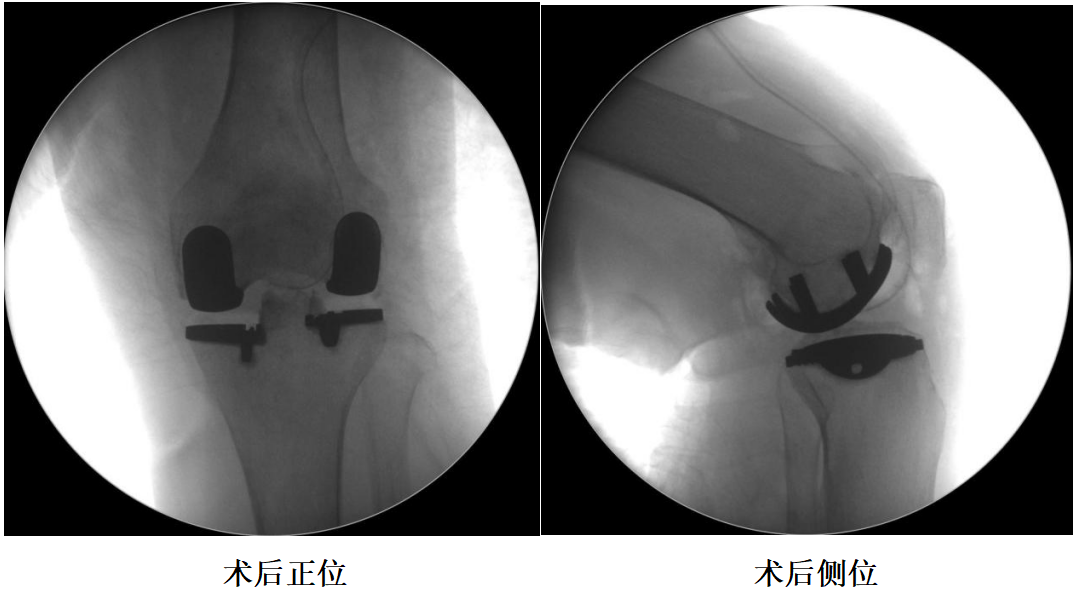

四、术后X透视片